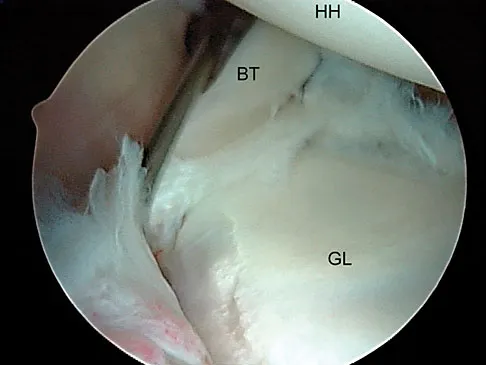

A 23-year-old man who is a competitive overhead athlete has shoulder pain. Based on the pathology shown in Figure 47, what treatment option would yield the highest satisfaction and return to overhead sports?

The patient has a classic type II SLAP tear that will respond best to arthroscopic repair. Labral debridement has been shown to lead to predictably poor results, and biceps tenodesis and tenotomy may be appropriate for an older patient who is not a competitive overhead athlete. Snyder SJ, Karzel RP, Del Pizzo W, et al: SLAP lesions of the shoulder. Arthroscopy 1990;6:274-279.